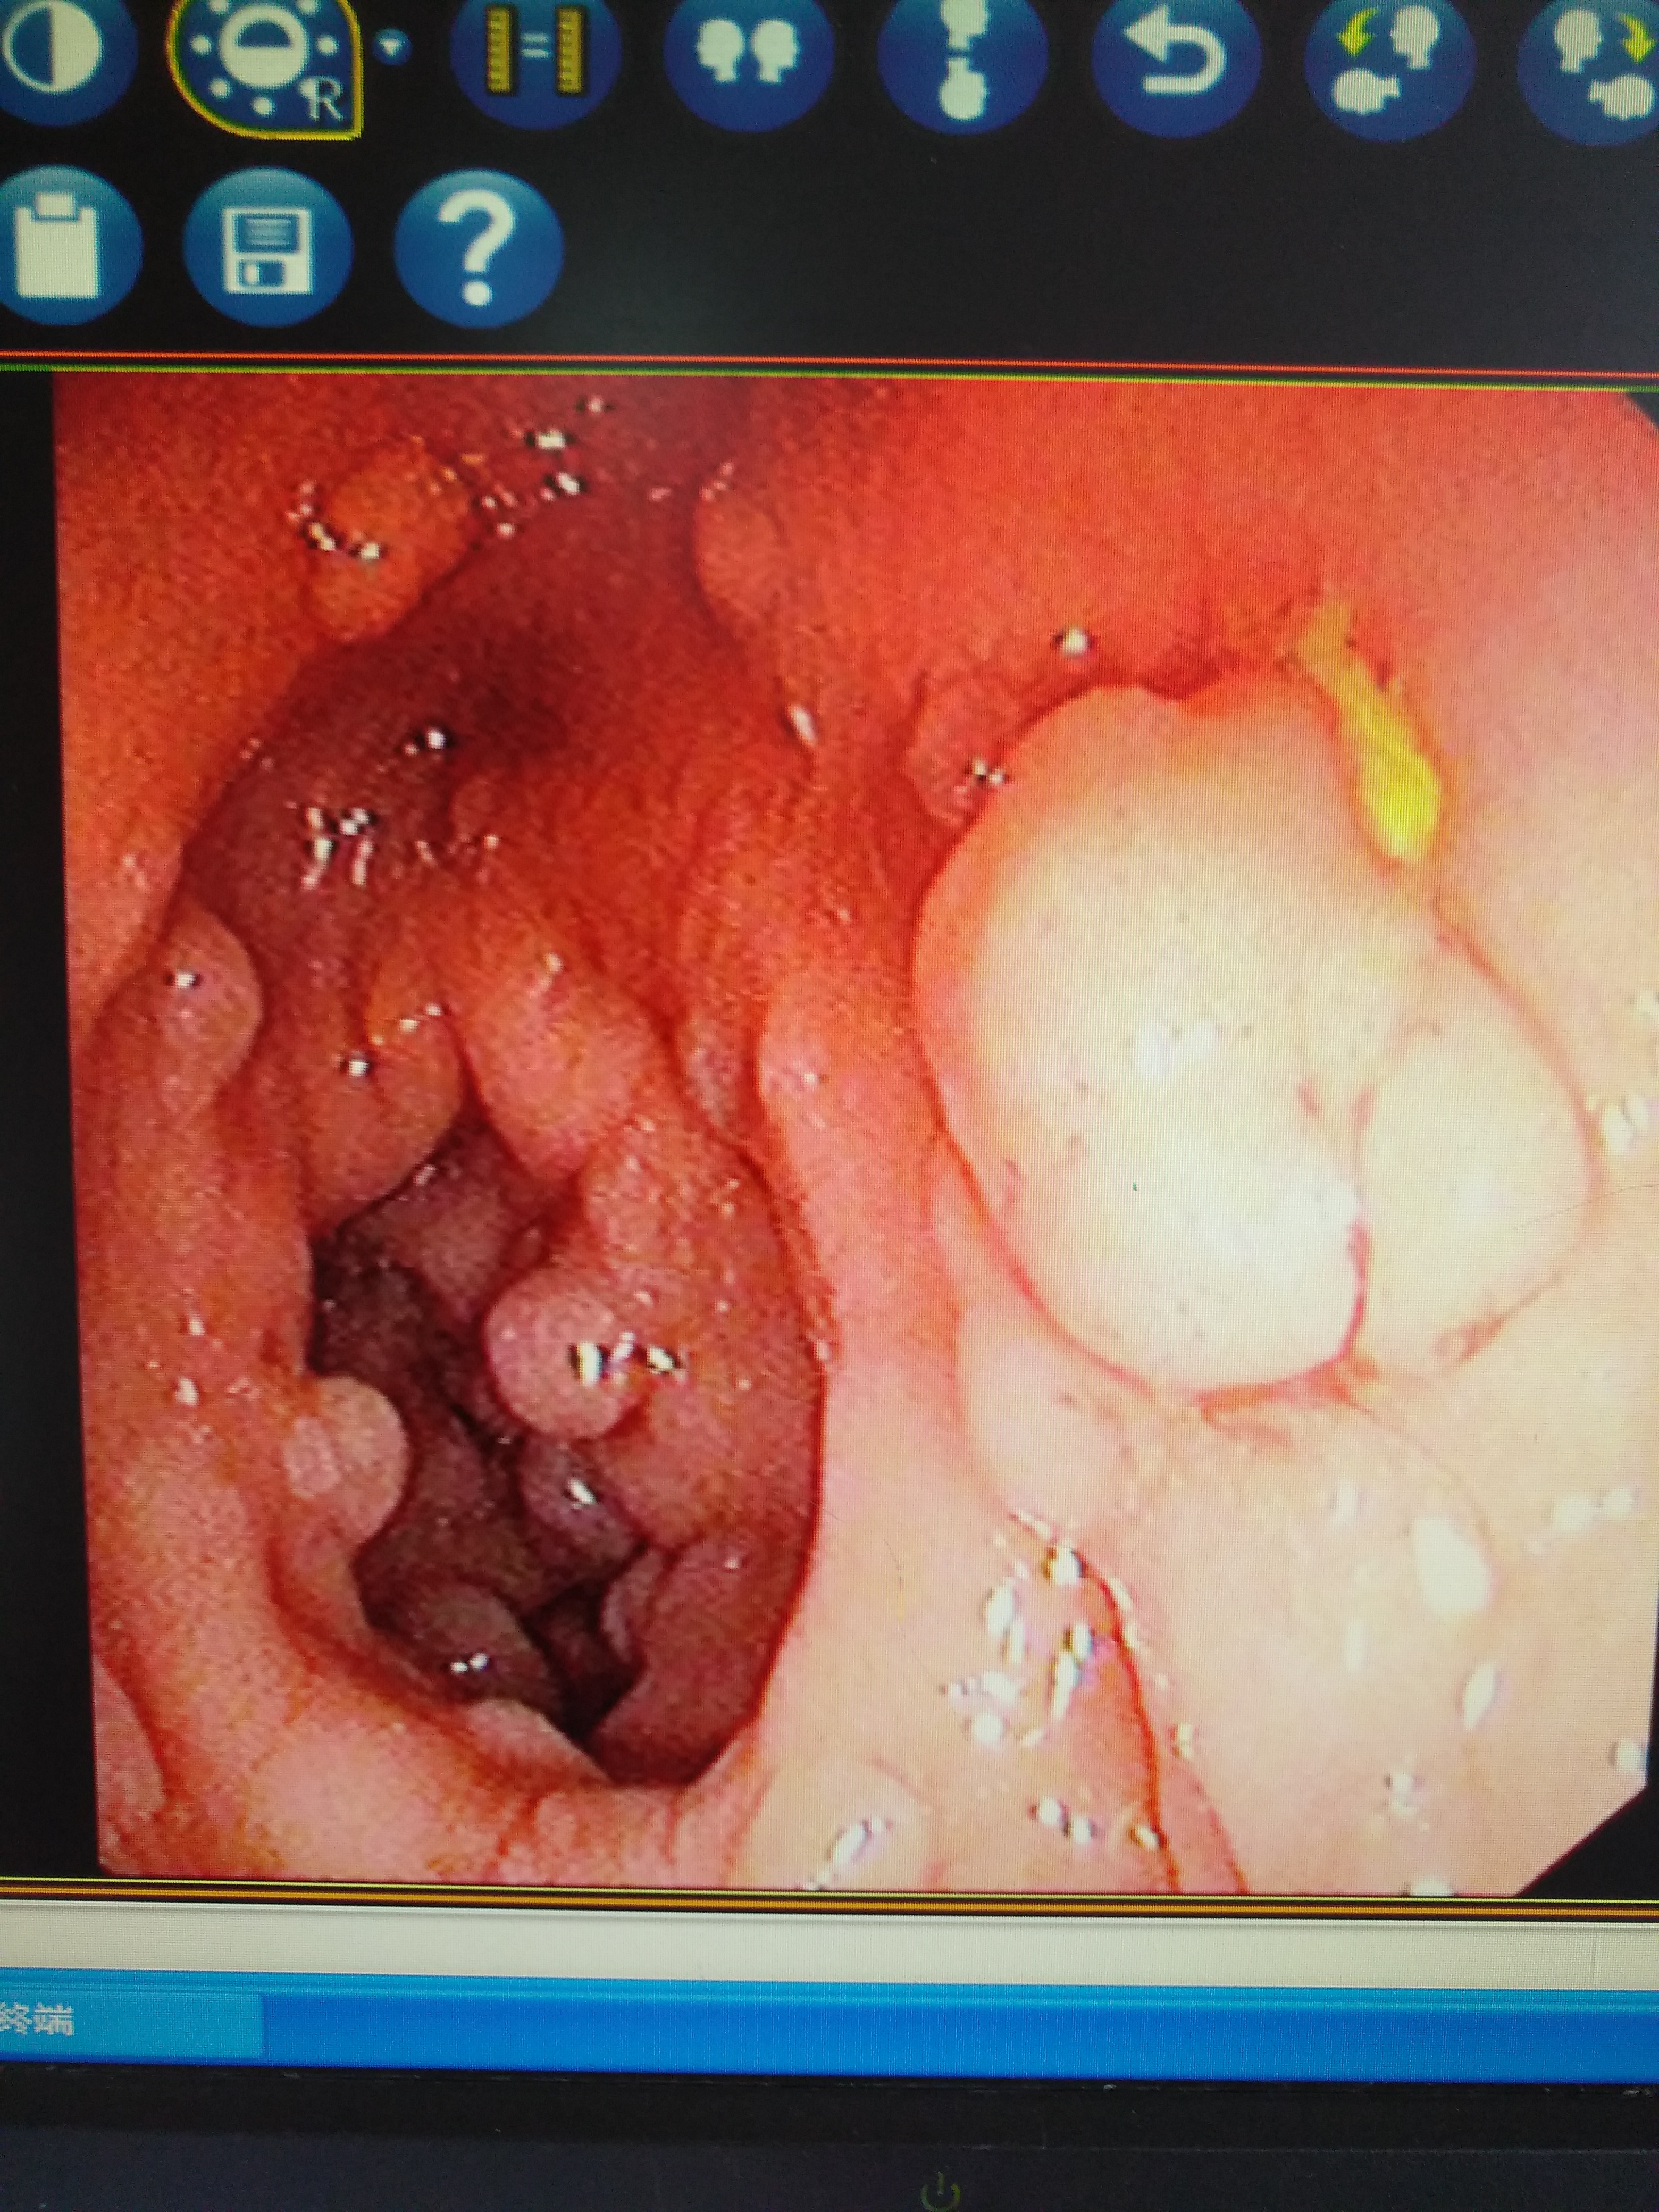

最近几年收治了一些特殊的病例,因为口唇发黑就诊,诊断考虑有胃肠道息肉,其实如果非胃肠专科的医生,可能都很少见得到这种病例。

它的学名叫做黑斑息肉综合征(波伊茨一耶格综合征,Peutz 一Jeghers syndrome )又称色素沉着息肉综合征。

它是一种常染色体显性遗传病,约50 %患者有明显家族史。主要表现为面部、口唇周围和颊钻膜的色素沉着,以及胃肠道多发息肉,病理上为错构瘤。

这种疾病通常除了口唇有黑斑以外,没有明显的症状,如果胃肠道息肉较大时会出现腹痛、便血症状,甚至可能会导致肠梗阻,肠套叠,贫血等症状,严重时危机生命。而且该疾病具有一定的癌变几率。

它的治疗一般可以通过肠镜下息肉切除,或者是手术切除等方法。 因为这种疾病比较罕见,而且有一定的家族遗传倾向,曾接诊过一家三口:父亲和两个女儿都患有这种疾病,并接受了治疗。